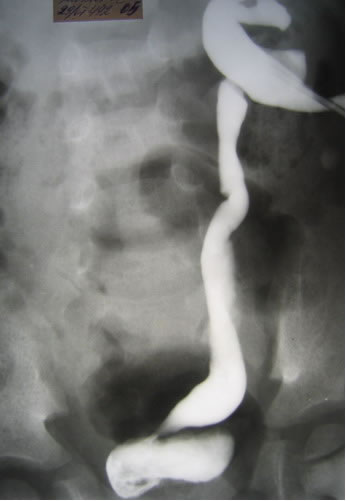

Антеградная уретерография справа

Антеградная уретерография слева